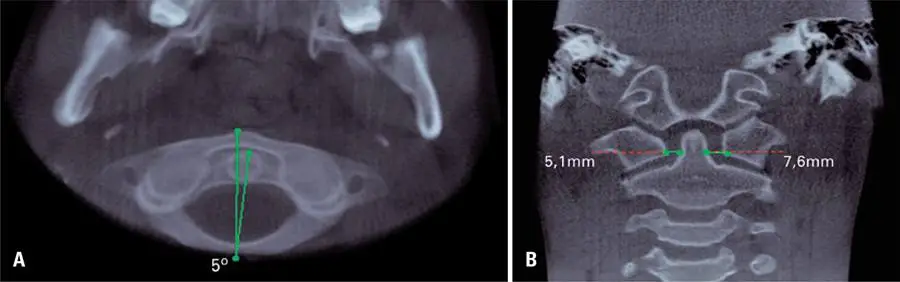

A instabilidade rotatória é caracterizada pela rotação entre os corpos vertebrais, sendo a causa mais comum de torcicolos em crianças.(-) Essa prevalência ocorre devido às características anatômicas específicas da infância, como desproporção entre cabeça-pescoço, musculatura cervical subdesenvolvida, frouxidão da cápsula articular, elasticidade ligamentar e formato horizontal das facetas articulares entre as vértebras atlas e axis.(-) Essa condição pode ocorrer devido a inflamação/infecção(,,) ou trauma,(,,,) ou ter origem neurogênica ou idiopática.()

O diagnóstico inclui exame clínico e imagiológico.(,) Entre os exames por imagem do tecido ósseo, as radiografias em projeções anteroposteriores e laterais são de uso limitado, pois não permitem uma visualização precisa dessa alteração, devido à dificuldades no posicionamento dos pacientes (desalinhamento da cabeça ou da fonte de raios X, e sobreposição de estruturas), levando à dificuldade na interpretação das radiografias.(,,) Já a tomografia computadorizada é considerada o padrão-ouro.(,,) Imagens de reconstrução tridimensional proporcionam uma visualização global da rotação, auxiliando no diagnóstico.(,,) Além disso, a ressonância magnética também pode ser solicitada para avaliar o risco de comprometimento do feixe vásculo-nervoso e injúrias dos ligamentos adjacentes às vértebras.(,-)